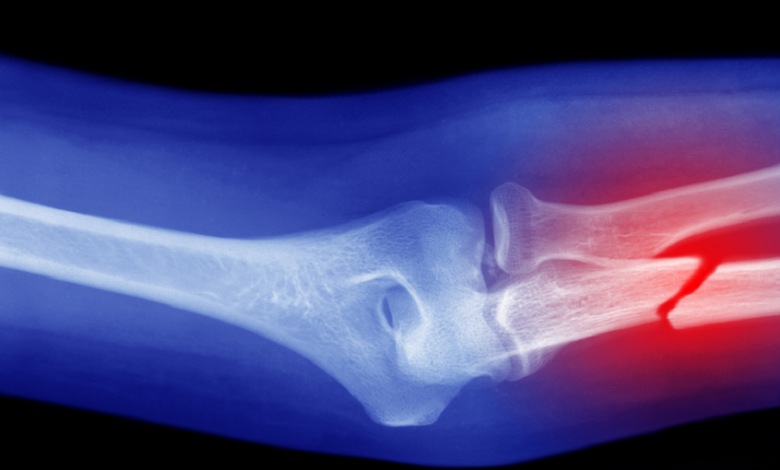

ابتكار جديد يساعد على ترميم العظام بسرعة

ابتكر فريق طبي من المعهد الفدرالي السويسري للتكنولوجيا في لوزان مادة شبيهة بالعظام, تساعد على ترميم العظام بسرعة وكفاءة أكبر.واستلهم الباحثون المادة من الخصائص الميكانيكية المرنة للعظام, وطوروا “حبرا” خاصا يمكن طباعته بتقنية ثلاثية الأبعاد أو حقنه ليصبح هياكل صلبة تشبه العظام الطبيعية.ويقوم هذا الابتكار على استخدام إنزيمات طبيعية لتسريع عملية التمعدن في درجة حرارة الغرفة, ما يقلل استهلاك الطاقة مقارنة بالطرق التقليدية التي تحتاج إلى حرارة عالية.ويعتمد الحبر المطور على أحد المكونات الأساسية للعظام, وهو معدن هيدروكسي أباتيت, يمكن الباحثين من إنتاج هياكل مسامية قوية وخفيفة الوزن خلال أيام قليلة.كما يعتمد الابتكار على إضافة جزيئات صغيرة من الجيلاتين الخالي من الإنزيمات, والتي تذوب تاركة مسامات داخل الهيكل. هذه المسامات تتيح للخلايا الطبيعية التغلغل ونمو عظام جديدة عند زرع الهياكل في موضع الكسر, ويمكن التحكم في حجمها وكثافتها لضبط مسامية الهياكل حسب الحاجة.وأظهرت التجارب أن إدخال مسامات تشكل نحو 50 بالمائة من حجم الهيكل, يخلق مساحة كافية لنمو الخلايا. وبعد 14 يوما من زرع الخلايا الجذعية البشرية, لاحظ الباحثون نمو الكولاجين وبروتين “أوستيوكالسين”, وهما مؤشران على تكوين عظام جديد, ما يثبت إمكانية استخدام هذا النهج في تجديد العظام بشكل طبيعي.